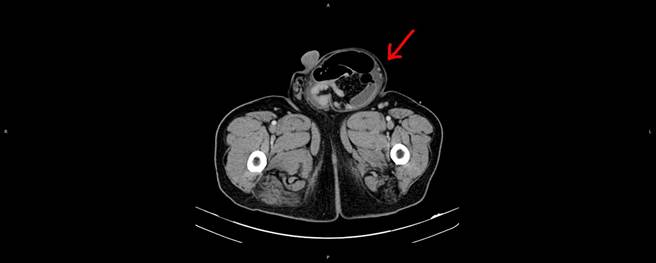

外科黄善鸿医师表示,透过电脑断层检查发现,病人的右侧腹股沟肿块直径达15公分,诊断为嵌顿性腹股沟疝气,且合併小肠阻塞、急性肾衰竭,小苹果已经变成大水梨了,要赶快手术处理,庄男经紧急接受肠道沾黏分离手术与疝气修补手术后恢復良好,肾衰竭已自行改善,也免于终身洗肾,庄先生10日后即顺利出院,庄男开心表示总算摆脱小苹果。

疝气发生的形态与手术治疗方式略有不同,初期通常可将突起部位推回腹腔,但若久未处理,又或者若器官组织掉落卡住的位置较特别,可能危及性命;例如肠道卡在疝气囊里,血液因无法顺利传送,可能造成器官组织缺血或坏死,形成「嵌顿性腹股沟疝气」,病人此时会有肚子疼痛、发烧、噁心、呕吐等症状,十分不适。尤其坏死的肠道容易导致肠穿孔、腹腔感染,造成病情加重,最严重可能导致败血症、穿孔性腹膜炎、休克、死亡,严重危及生命,是腹部的急症,需要立即手术。